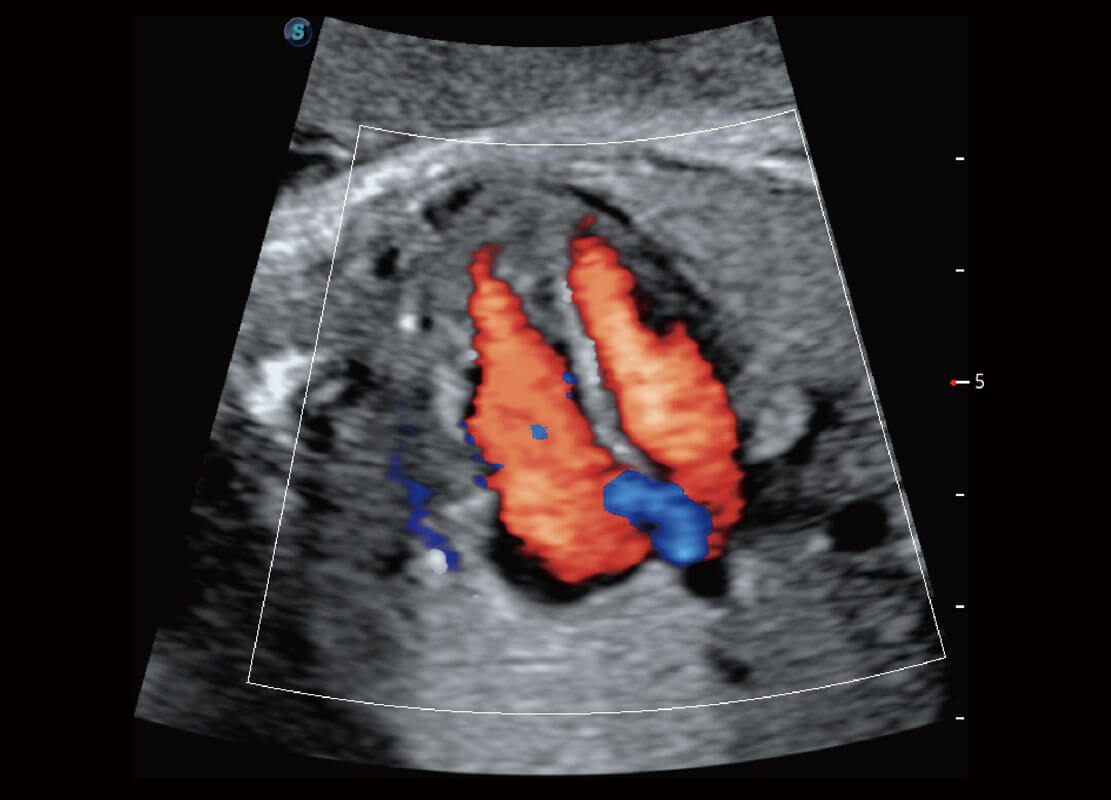

胎心筛查

P60搭载一系列胎儿心脏成像技术,实现更精细的胎儿心脏评估。

• 四腔切面

• 四腔心血流

• 右室双出口

• 胎心容积成像